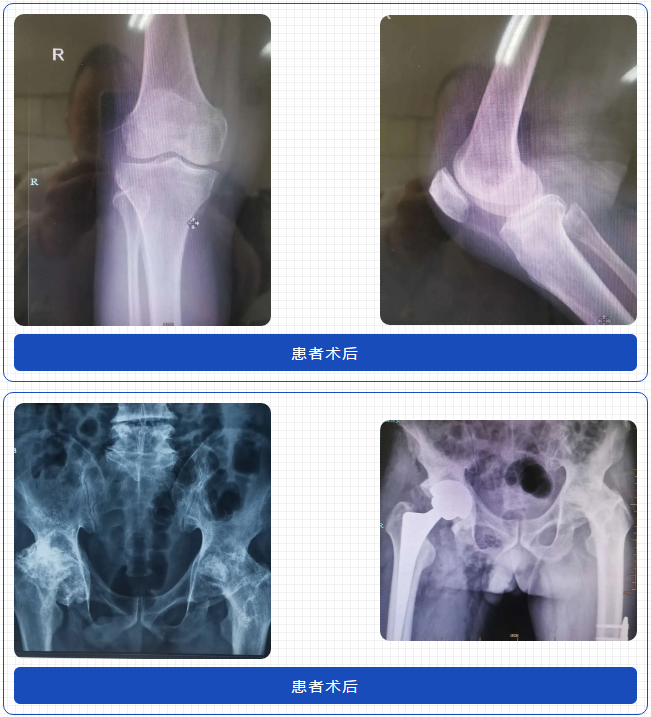

學(xué)術(shù)分享完成后,馬上帶領(lǐng)學(xué)員開(kāi)展三臺(tái)換膝和一臺(tái)換強(qiáng)直髖手術(shù)的現(xiàn)場(chǎng)教學(xué)。孫院長(zhǎng)憑借嫻熟的技術(shù)平時(shí)十幾分鐘就可以完成一臺(tái)換髖手術(shù),而在手術(shù)教學(xué)現(xiàn)場(chǎng),孫院長(zhǎng)循循善誘引導(dǎo)在場(chǎng)的醫(yī)生思考,耐心講解每個(gè)步驟和技術(shù)難點(diǎn)及解決方案。孫院長(zhǎng)像一盞燈一樣,把自己精湛技術(shù)毫無(wú)保留的教授給大家,彰顯了一位大師醫(yī)者的博大胸懷,令同行敬仰。